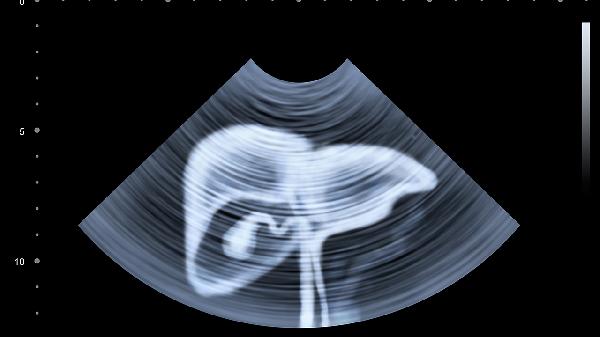

超声引导下胆囊穿刺引流术后如何护理

超声引导下胆囊穿刺引流术后护理需重点关注引流管维护、伤口管理、活动限制、饮食调整和并发症监测五个方面。